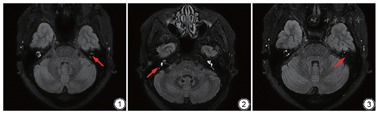

在3D T2WI DRIVE序列和3D FLAIR序列图像上,由2名5年以上放射诊断工作经验主治医师采用双盲法对重建图像评分,如有冲突,经讨论达成一致性意见。具体评分方法参考赖艳梅等[12]的积分评定方法:(1)半规管不显影0分,部分显影1分,完整显影2分。(2)前庭内无高信号区为0分;前庭内有高、低信号区,其中低信号区向下超过该平面为3分,低信号区局限于水平半规管下缘平面以上为6分;耳蜗底转不显影0分,部分显影且前庭阶面积小于鼓阶1分,不小于鼓阶2分,底转完整显影3分;耳蜗中转不显影0分,部分显影1分,完整显影2分;耳蜗顶转不显影0分,显影1分。在本研究中,符合外淋巴间隙的MRI钆造影评分总分在14.5分以下、前庭内的低信号评分在3分及以下、半规管的得分在4分以下中任意一点则诊断为膜迷路积水(阳性)[12]。前庭内的低信号评分在3分及以下诊断为前庭积水(阳性)(图1~3)。

巴显影明显减弱;右侧前庭球囊及椭圆囊扩大,右侧耳蜗轻度扩大,半规管部分显影。左侧耳蜗、前庭显影清晰,未见明显内淋巴积水征象。耳蜗膜迷路积水评分为3,前庭积水评分为2。图3 男,49岁,左耳MD患者内耳MRI钆造影。内耳MRI钆造影结果显示内淋巴间隙为低信号(箭),外淋巴间隙未显影;半规管下缘、前庭未显影,前庭重度积水。耳蜗膜迷路积水评分为2,前庭积水评分为2。